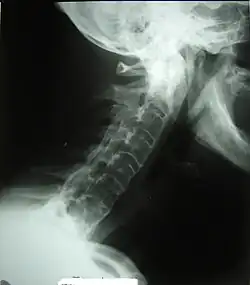

Veränderungen der Halswirbelsäule bei Morbus Bechterew

Der Krankheitsverlauf ist sehr variabel: Er reicht von leichter Steifheit bis hin zur kompletten Verschmelzung der Wirbel mit damit einhergehender Bewegungseinschränkung des Oberkörpers, beidseitiger Arthritis des Hüftgelenks, Arthritis der Gelenke in den Gliedmaßen und Manifestationen außerhalb der Gelenke. In typisch verlaufenden unbehandelten Fällen treten charakteristische Veränderungen an der Haltung des Patienten auf. Die Lendenlordose (Vorwärtskrümmung) der Wirbelsäule verschwindet, die Gesäßmuskeln verkümmern (Atrophie) und die Kyphose (Rückwärtskrümmung) der Brustwirbelsäule wird ausgeprägter.